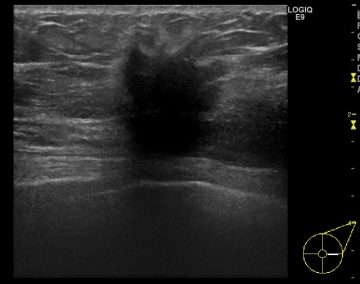

「エコーでも乳腺が白く、脂肪が黒く写るのですが、腫瘍が黒く写るので、

結局判別しにくいことに差はないんです。またエコーの場合、技師による技術の差がありますのでなんとも……。

超音波検診(エコー)の画像/画像提供:東京クリニック 乳腺外科